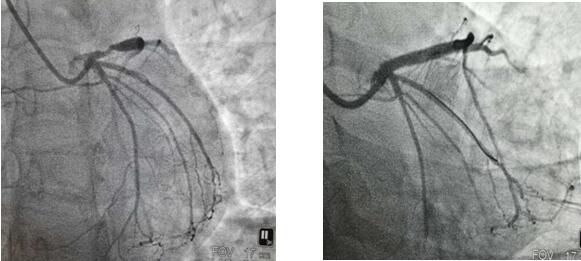

4月22日上午,患者王女士因“反復胸痛、胸悶半年”就診我院,行冠脈造影提示LAD段嚴重狹窄,經全面評估患者病情,充分結合患者及家屬意愿后,今日上午為31歲的王女士成功植入生物可吸收支架一枚,手術過程順利,術后效果滿意。

支架植入前 支架植入后